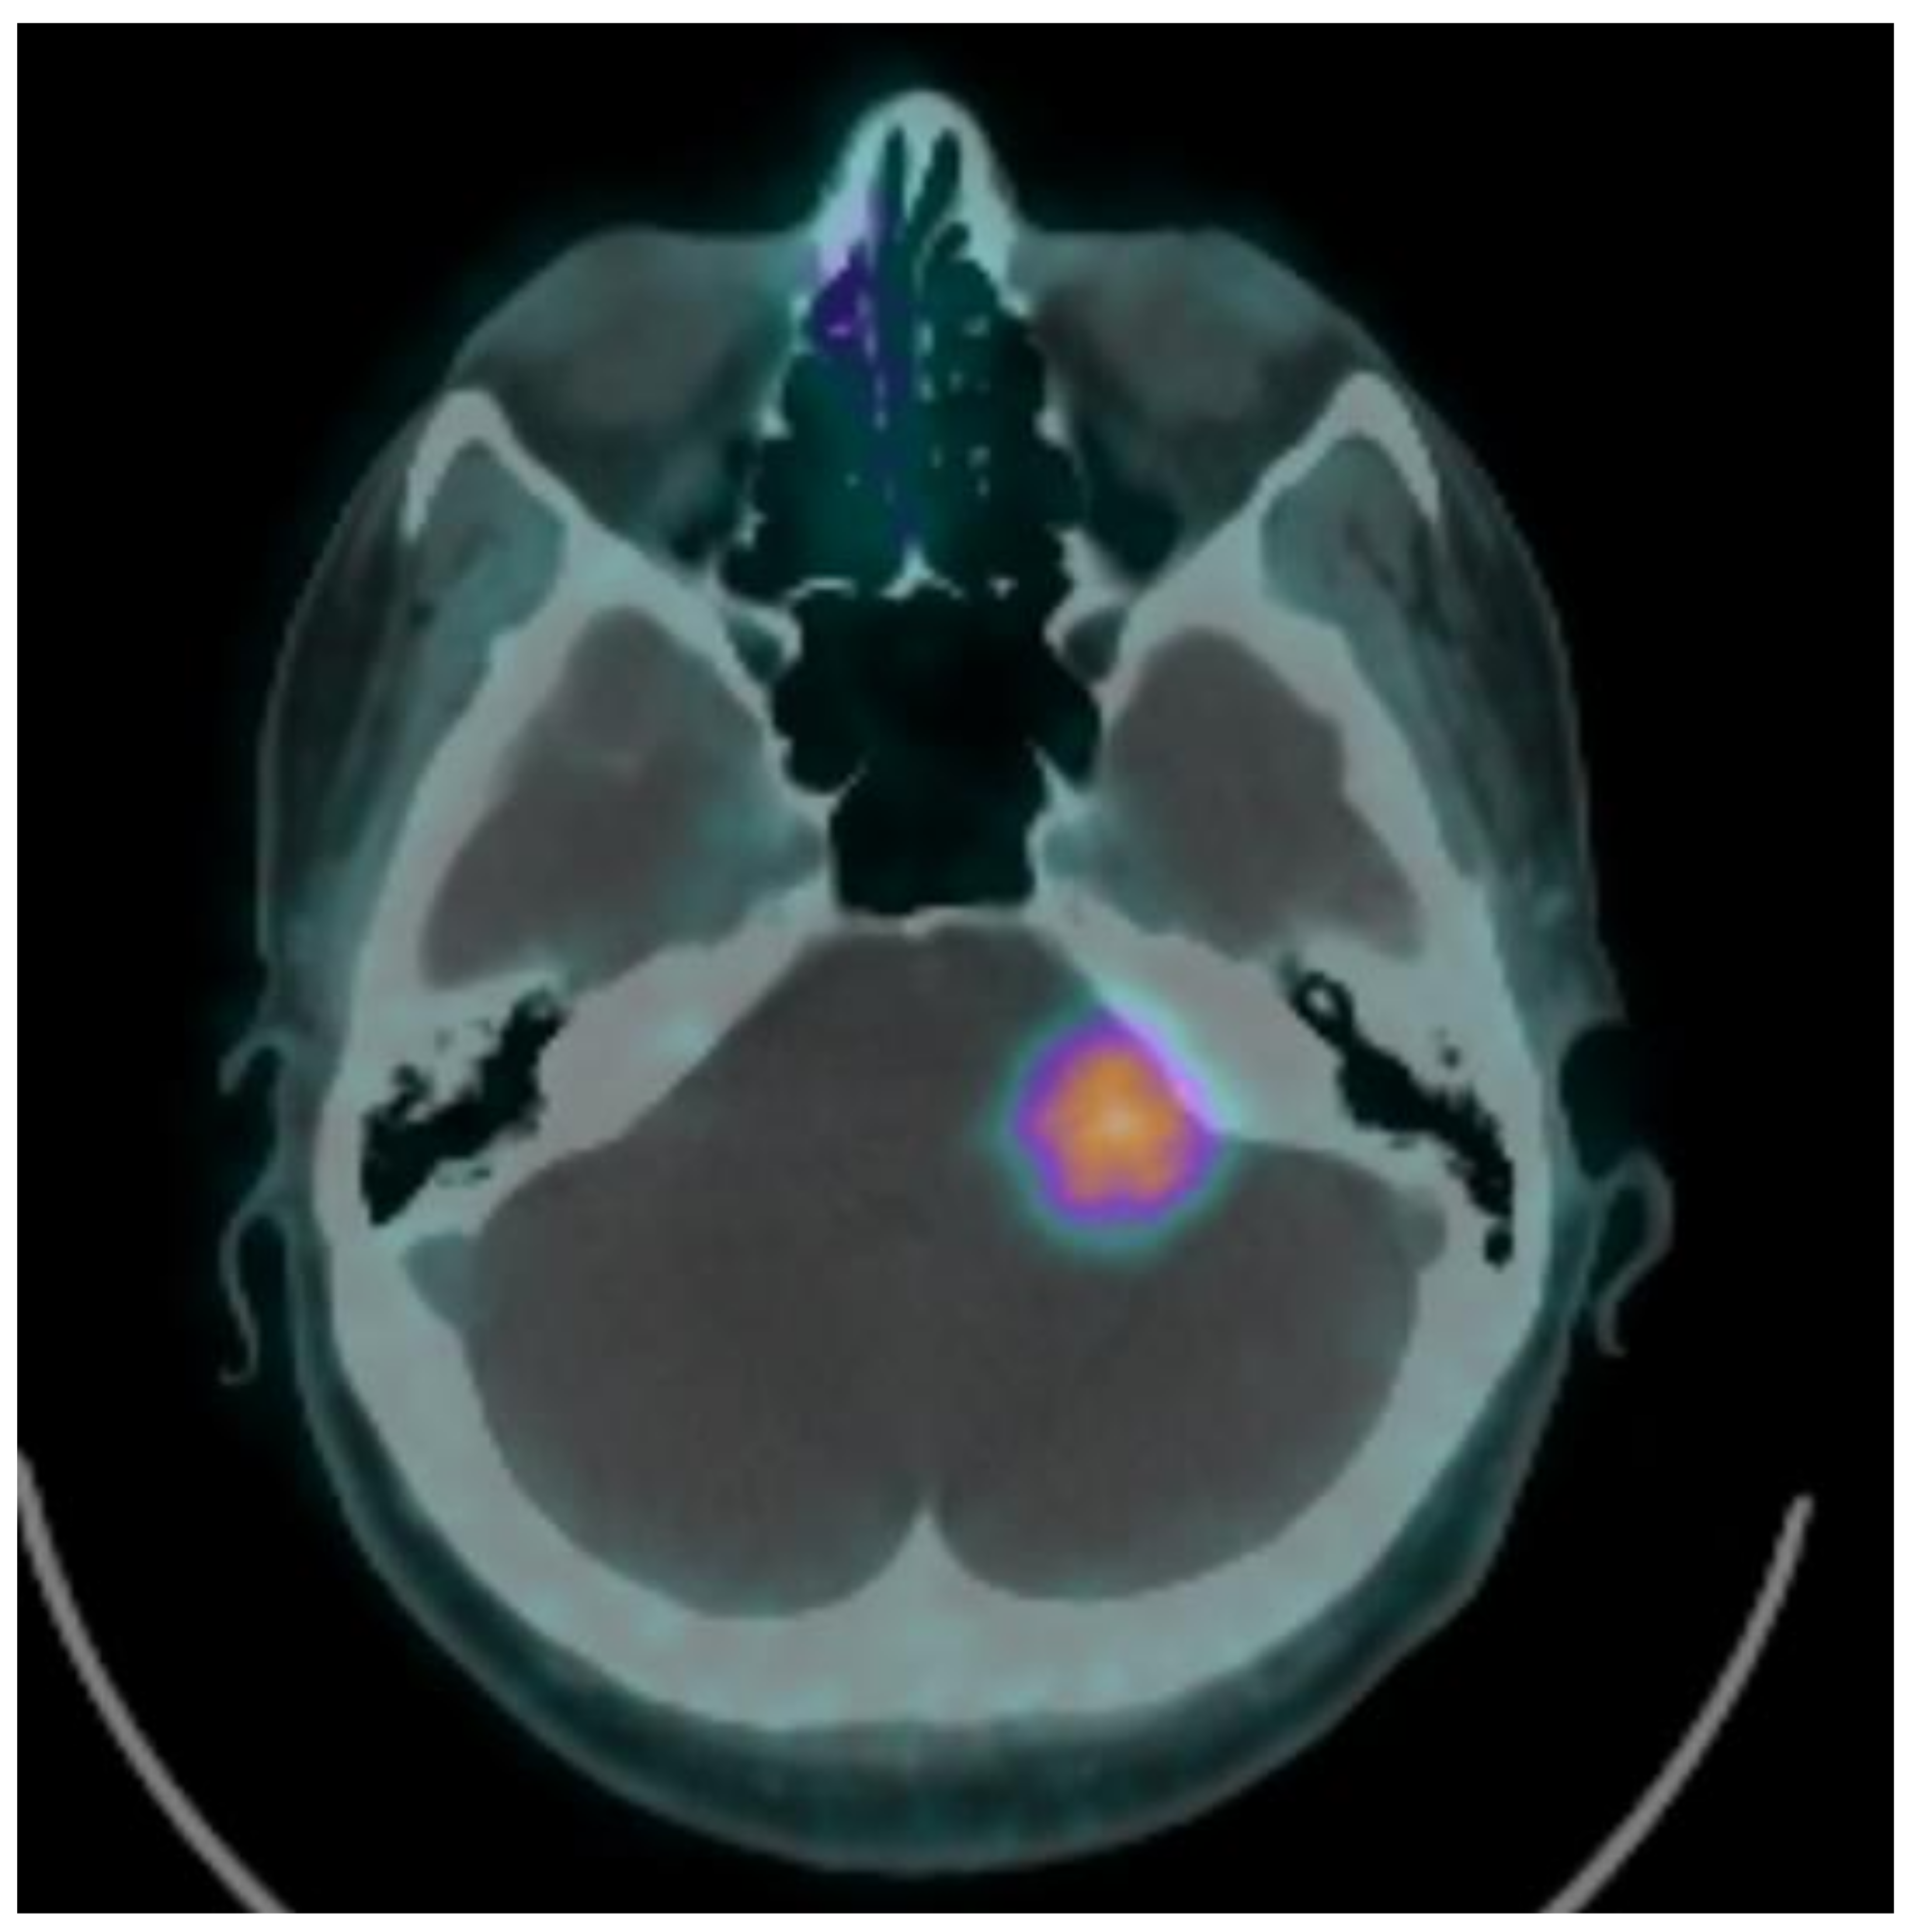

| 2 | 56 | female | left cerebellar | 1.310 | 9.41200765 | 14 | 3.5 | 18 | 2.6 | −26% | 14.0 |

| 16 | 52 | female | left cerebellar | 2.35 | 54.3340367 | 13 | 2.9 | 13.0 | |||